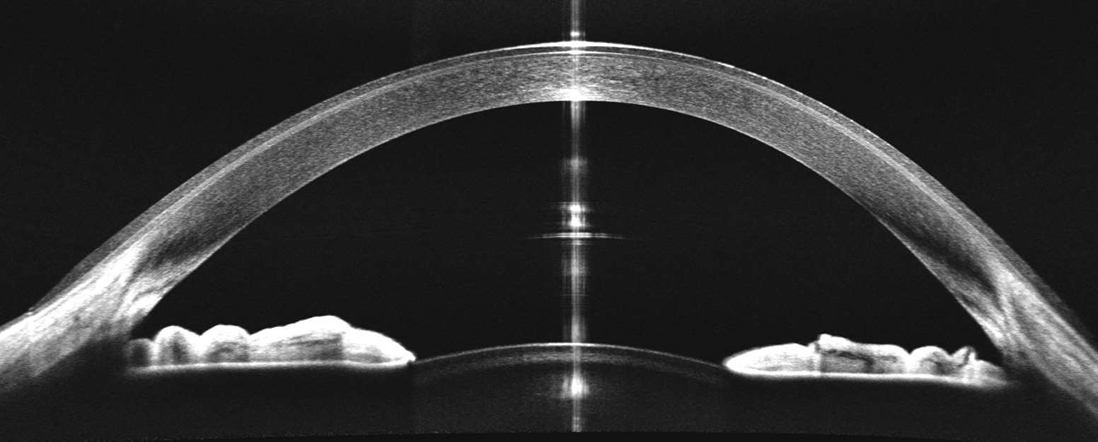

- Biométrie OCT : B-OCT® est une méthode innovante d'utilisation du dispositif OCT postérieur pour mesurer la structure oculaire le long de l'axe de l'œil. Un calculateur IOL est également disponible.

- Analyse Chambre Antérieure.